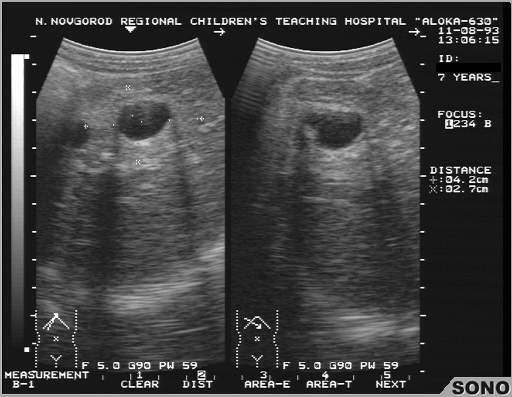

Эхинококковое поражение печени